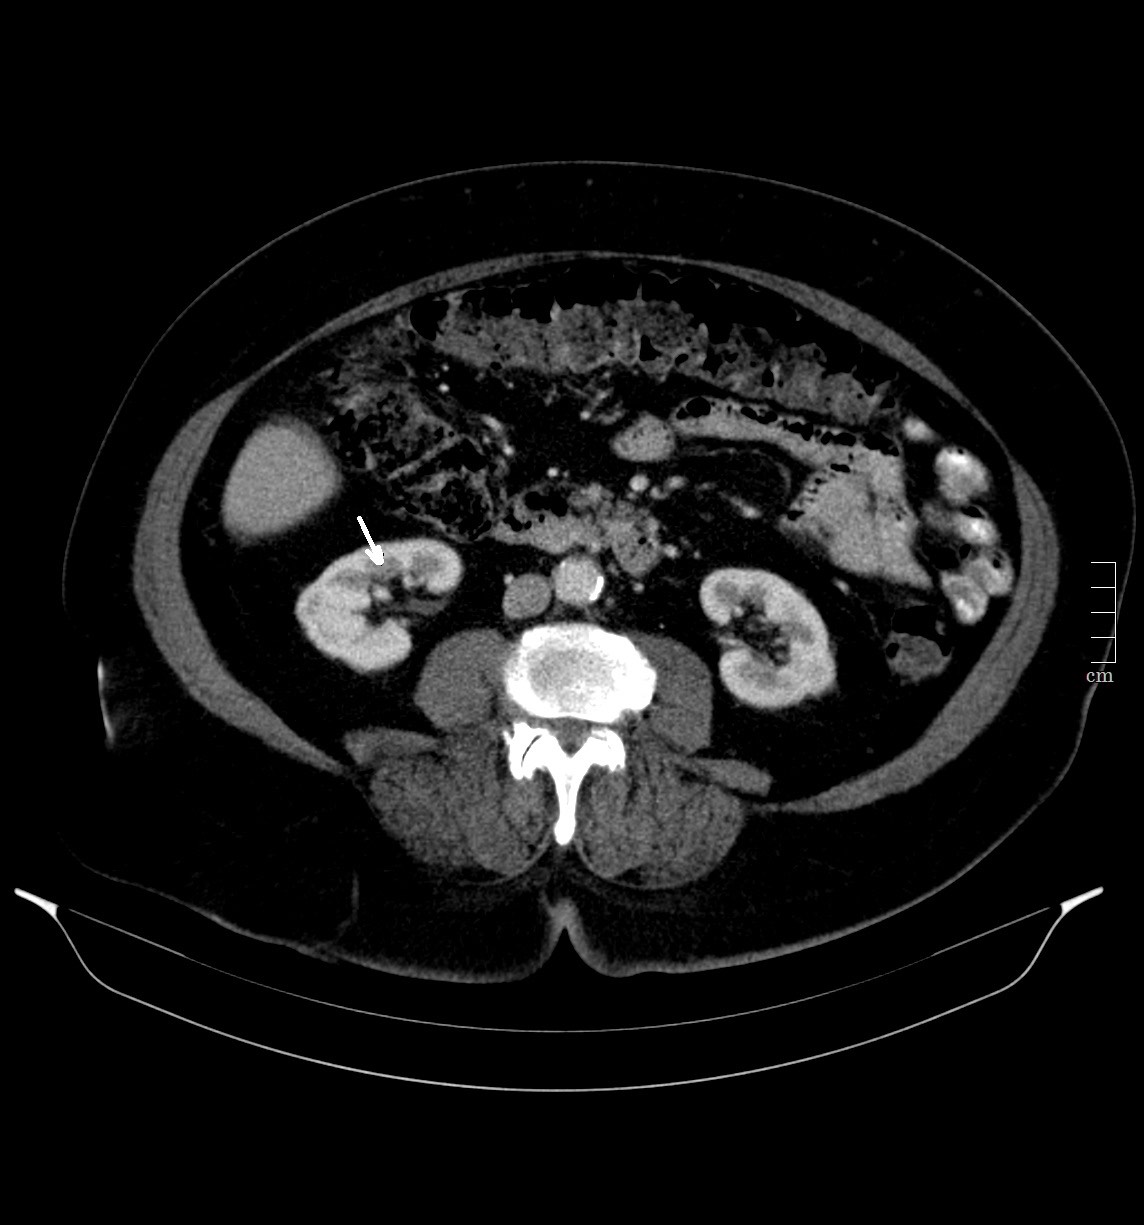

2903. Структура, указанная стрелкой, является